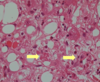

Zone 3 damage (centrilobular) – damage for substances that require bioactivation…

- Hypoxic damage (blood lost quite a lot of oxygen by the time it passes through zones 1 and 2)

- Metabolised hepatotoxic substances

- Zone 1 and 2 cells look similar at first but zone 3 are the most metabolically active cells in the liver